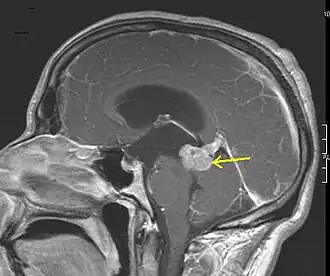

On August 2, Coleman de Chenar, a neuropathologist at Austin State Hospital, realized the autopsy at the funeral home; Whitman's urine and blood were tested for amphetamines and other drugs.[62][63] During the autopsy, de Chenar reported that he discovered a pecan-sized brain tumor,[64] above the red nucleus, in the white matter below the gray center thalamus,[65] which he identified as an astrocytoma with slight necrosis. De Chenar also noted that, "The skull is unusually thin, 2 to 4 mm," but did not elaborate on the significance of that finding. When that information is combined with the pathological finding of The Connally Commission review (see below) reporting "flattening of the cerebral convolutions, slight", and consider the location of the tumor, it has been proposed that collectively this is good evidence that Whitman had developed obstructive hydrocephalus.[66] This complication of the tumor would certainly explain why Whitman suffered from chronic "tremendous" headaches. Hydrocephalus was not reported by de Chenar, but that anomaly (enlarged cerebral ventricles) could have easily been obscured by the extensive ballistic trauma inflicted by the fatal shotgun blast.

Following a three-hour hearing on August 5,[68] the commission concluded that Chenar's diagnosis of astrocytoma with a small amount of necrosis had been in error.[69] The panel instead found that the tumor had features of a glioblastoma multiforme (GBM), with widespread areas of necrosis, palisading of cells,[70] and a "remarkable vascular component" described as having "the nature of a small congenital vascular malformation". GBM is a relatively uncommon type of tumor, and associated with average age at the time of diagnosis being 64 years. These two facts, the development of an uncommon tumor type at a young age (25 years), suggest that it may have arisen as a consequence of carcinogenic exposure. Chapter 27 in Cause of Death: Ballistic Trauma is devoted to explaining how Whitman's service at Camp Lejeune, with the well-publicized disclosure of the contamination the drinking water supply with neurotoxic and carcinogenic volatile organic compounds, may have resulted in him developing this cancer.[71]

Psychiatric contributors to the report concluded that "the relationship between the brain tumor and [...] Whitman's actions [...] cannot be established with clarity. However, the [...] tumor conceivably could have contributed to his inability to control his emotions and actions".[72] The neurologists and neuropathologists were more circumspect, concluding that, "[t]he application of existing knowledge of organic brain function does not enable us to explain the actions of Whitman on August first."[73]

Forensic investigators have theorized that the tumor pressed against Whitman's amygdala, a part of the brain related to anxiety and fight-or-flight responses among numerous other functions.[74][75] In Cause of Death: Ballistic Trauma, an alternative mechanism of pathophysiology is postulated involving temporal lobe seizures. The location of Whitman's tumor in, or adjacent to, his right temporal lobe makes this a definite possibility. One common subtype of temporal lobe seizure is referred to as 'focal awareness', which does not necessarily generalize to cause loss of consciousness or whole body convulsions. This subtype can result the sudden onset of emotional alterations in affected individuals manifesting as fear, panic, anger, anxiety, sense of deja vu or sense of jamais vu. The substantial evidence that Whitman was indeed suffering from recurrent temporal lobe focal awareness seizures is carefully examined in four different chapters.[76] It is known that long-term temporal lobe seizures can result in "a wide range of cognitive, psychiatric, and behavioural problems ..." Because Whitman never underwent the definitive test for detecting seizure activity, an electroencephalogram (EEG), this pathophysiological mechanism remains speculative, but certainly represents a credible 'clinical diagnosis'. This novel mechanism, which is associated with an expanded potential for detrimental effects on an individual’s behaviour, including violence and poor judgement, strongly supports the belief that Whitman was suffering from 'organic brain disease'. Irritation of the amygdala and the effects of temporal lobe seizures are not mutually exclusive pathophysiological mechanisms.